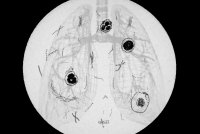

The Path to a Better Tuberculosis Vaccine Runs Through Montana

Researchers at the University of Montana have pitched in to develop a more effective vaccine in the fight against an ancient disease that still kills an estimated 1.6 million people a year worldwide.